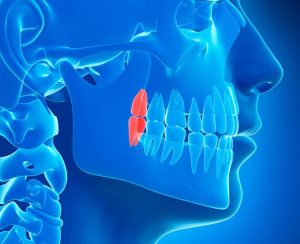

Wisdom teeth are the third set of molars that typically emerge in a person’s mouth between the ages of 17 and 25. They are the last teeth to develop and are located at the very back of the upper and lower jaws. While some individuals may have all four wisdom teeth, others may have fewer, or even none at all. The eruption of wisdom teeth can sometimes cause issues, such as impaction, overcrowding, or infection, which may necessitate their removal to maintain optimal oral health. In cases where wisdom teeth emerge without complications, they can function as normal molars, assisting in chewing and grinding food.

In some cases, wisdom teeth may only partially emerge, leaving a flap of gum tissue covering the tooth. This flap can trap food particles and bacteria, leading to gum infections, further exacerbating the pain and swelling. Impacted wisdom teeth, where the tooth does not have enough space to emerge correctly, can also be a source of discomfort. Impacted teeth may grow at an angle, pressing against other teeth, and potentially causing damage to the surrounding dental structures.